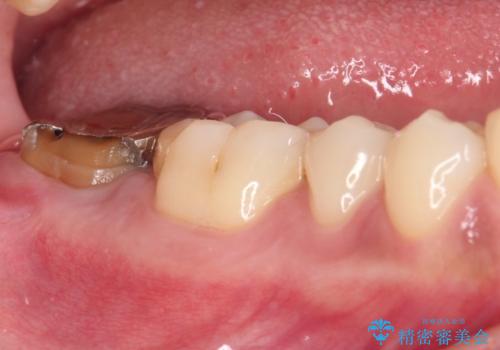

被せものが入れられない 外科処置を行ったセラミック治療

- 奥歯の虫歯治療を希望したものの、歯の高さが足りなくて治療ができないと言われ、来院された患者様です。

レントゲン撮影より、根尖部に病変が認められたため、根管治療を行った後に、歯冠長延長術を行うこととしました。